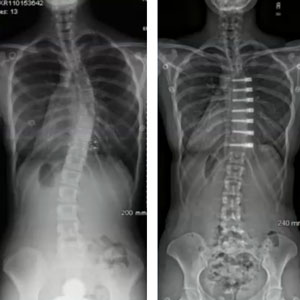

Patient Success Stories

Stephanie

38 Degree Curve

Marcia

Adult Scoliosis

Taylor

53 Degree Curve

Sheila

Flatback Syndrome

Rachel

78 Degree Curve

Brinn

51 Degree Curve

Lindsay

54 Degree Curve

Jacobe

55 Degree Curve

Carlie

Cindy

Cody

48 Degree Curve